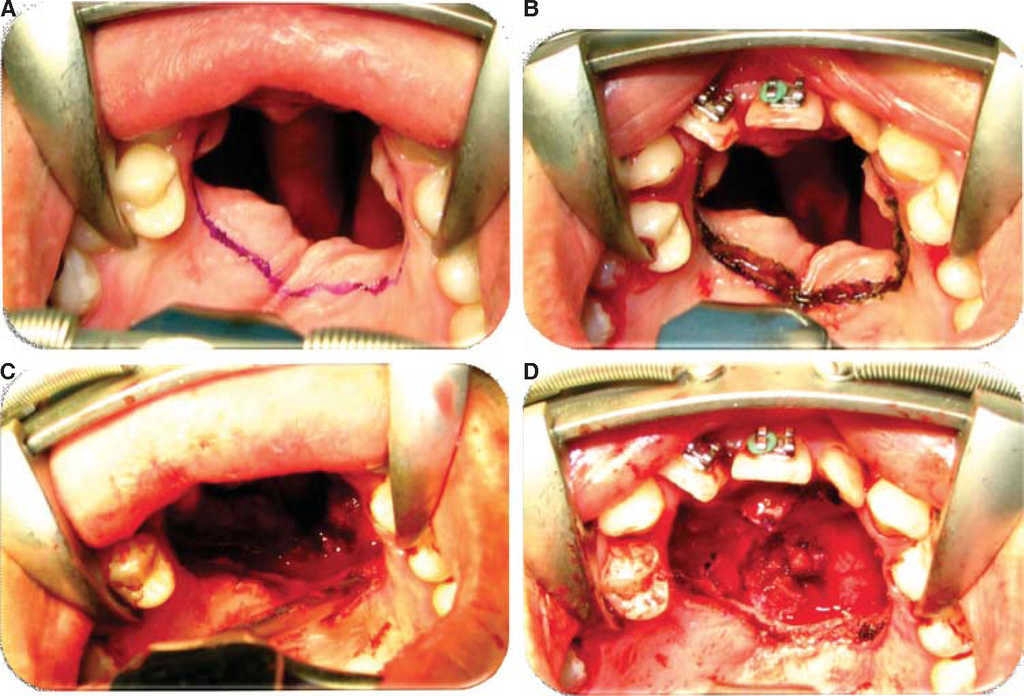

Oronasal fistula surgical closure was programmed with anterior based tongue distanced flap. Under general anesthesia with naso-tracheal intubation, palate and donor site were infiltrated with lidocaine and epinephrine at 2% and 1:100,000 to achieve hemostasis. A Digman type mouth prop was placed. A peri-fistular incision was executed with number 15 surgical blade and electric scalpel. The defect's borders were dissected and everted and then sutured with 910 4-0 polyglactine, 100% closure was achieved in the nasal mucosa plane. Nasal irrigation was undertaken with physiological solution, no egress of liquid was observed from the sutured defect. The Digman type mouth prop was removed and a Mackinson mouth opener was placed. The tongue was pulled with one 2-0 silk suture point at the tongue's tip. The anterior-based tongue flap was designed so as to be of a size 20% larger than the defect and with an approximate length of 5 cm, taking great care to cover the whole defect and avoid tension. Hemostasis was achieved with electrocautery and with polyglactin 910 sutures. Suturing of donor site was executed in two planes with 4-0 polyglactin 910; no hematomas were observed. The tongue flap was rotated over the defect and sutured over the defect borders with polyglatin 910 simple stitches. Surgical event was completed without complications or accidents (Figures 2, 3, 4). No inter-maxillary fixation was applied since, due to his age, the patient was considered to be cooperative.

Figure 3 A. Design of anterior-based tongue flap. B. Incision with number 15 scalpel blade. C. Flap dissection at 7mm thickness including mucosa and muscle. D. Dissected flap. E. Suture of donor bed.